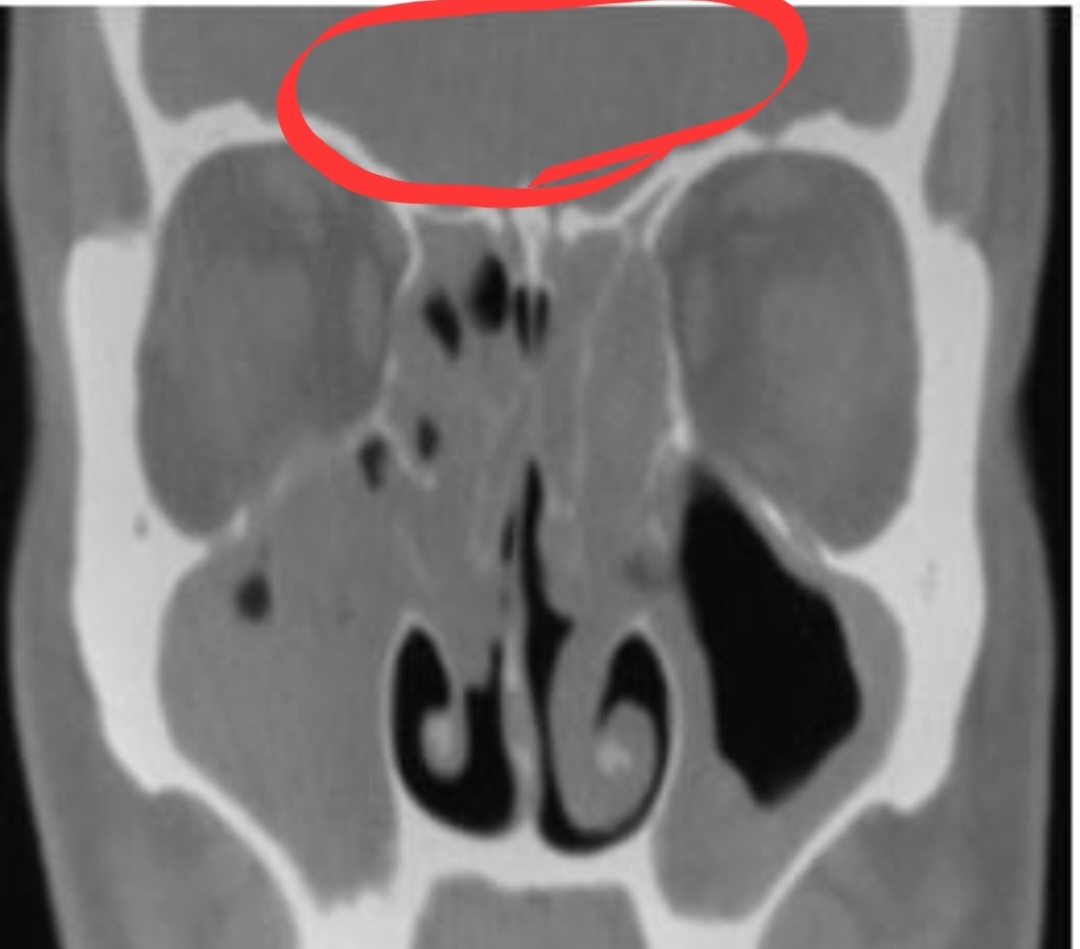

2) 두 번쨰 사진: 이마쪽에 빨간색으로 동그라미 친 부분

저 부분도 원래 저렇게 회색으로 채워져 있으면 안됩니다. 검정색으로 보여야 정상안데 저 이마 부분도 검은색 부분이 없는 것으로 보아 고름, 농(염증)으로 꽉 차 있는 것입니다.

그리고 3번 째 말씀드릴 곳은 양쪽 눈 사이 부분인데요, 그것은 아래 사진 보시면 2번으로 적어놓은 부분입니다. 엑스레이 사진에서 눈 사이 부분을 보시면 검은색 부분이 몇 군데 보이는데 저기도 원래 부비동으로 빈 공간이기 때문에 검정색으로 보이는게 정상입니다.

검정색은 농이 차 있지 않고 공간이 뻥 뚫려 있다는 의미에요. 위 엑스레이 사진으로 봐서도 양쪽 눈 과 코 사이 부분도 농으로 차 있는것으로 보입니다.

아래 사진으로 보시면 더 쉽게 이해가 되실겁니다. 1번, 2번, 3번으로 표시하여 설명해 놓았으니 아래 사진과 설명을 천천히 읽어보시기 바랍니다.

위 사진에 이해하기 쉬우시라고 부비동을 크게 1번~3번으로 써 놓았습니다. 이마 위 2곳, 눈과 코 사이 2곳, 양 볼 쪽에 2곳 총 6곳이 엑스레이를 찍었을 때 검은색으로 나타나야(고름이 없고 비어 있어야) 축농증 없는 정상 상태입니다.

제가 엑스레이를 찍었을 때도 공교롭게 위에 올려드린 엑스레이 사진과 비슷했던것 같은데 제가 저는 눈 옆에 농으로 더 꽉 차 있었고 오른쪽 볼쪽에 보이는 검은색 부분도 더 작게 나왔었습니다. 저분보다 제가 더 심했던것 같습니다.

의사선생님께서 특히 눈 옆 쪽에 찬 농을 보시면서 말씀하시기를 제 축농증 케이스가 복잡한 축농증 케이스라고 하셨습니다. 알레르기성 비염이 있어 면역력이 떨어지거나 계절, 온도에 따라 알레르기 반응이 나타나면 바로 재발하는 케이스라고 하셨습니다.